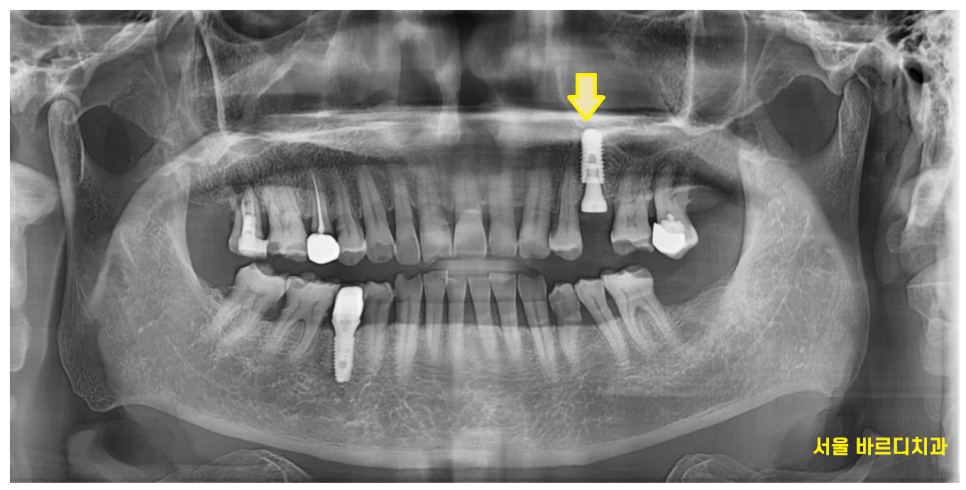

24.02.07

금니 빠짐으로 내원하셨고

임플란트 치료로 완료해드렸습니다.

기존 금니는 웃을 때 보이실 수 있어서

요즘 대세

하얀 색깔 보철로 치료를 끝내드렸습니다.

완성~!